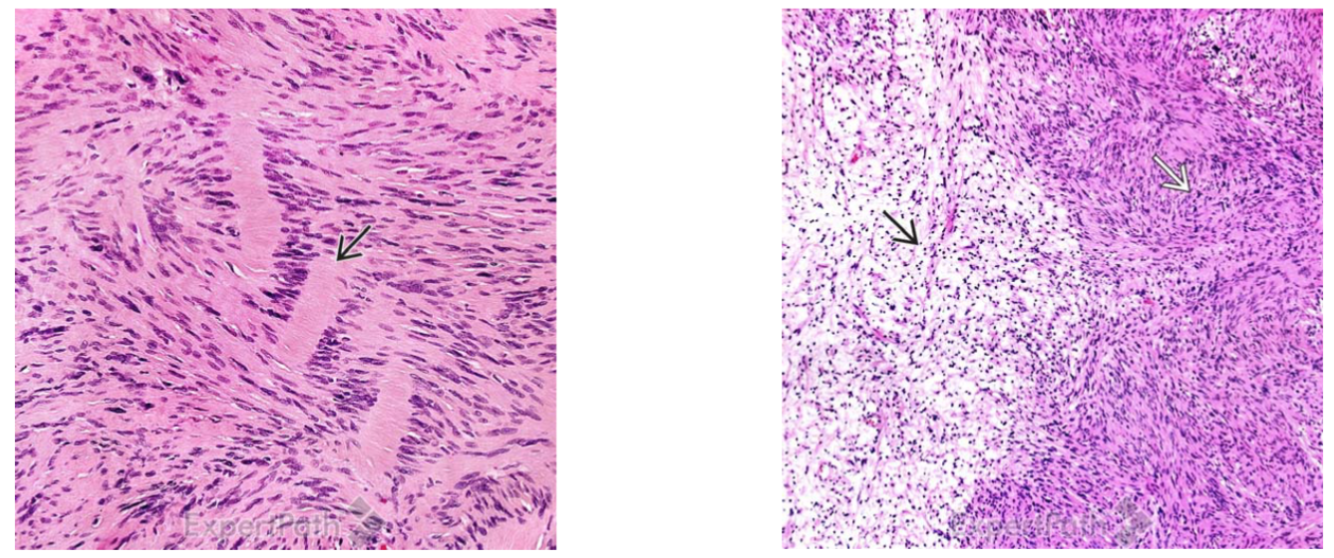

The provided microscopic samples are from what larger pathology? Describe the two samples.

Schwannoma